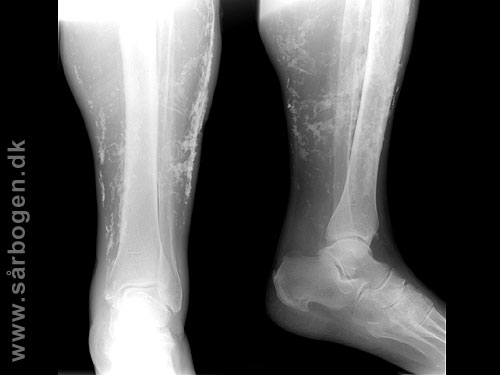

Zoom

Charcot i ankel (rtg...